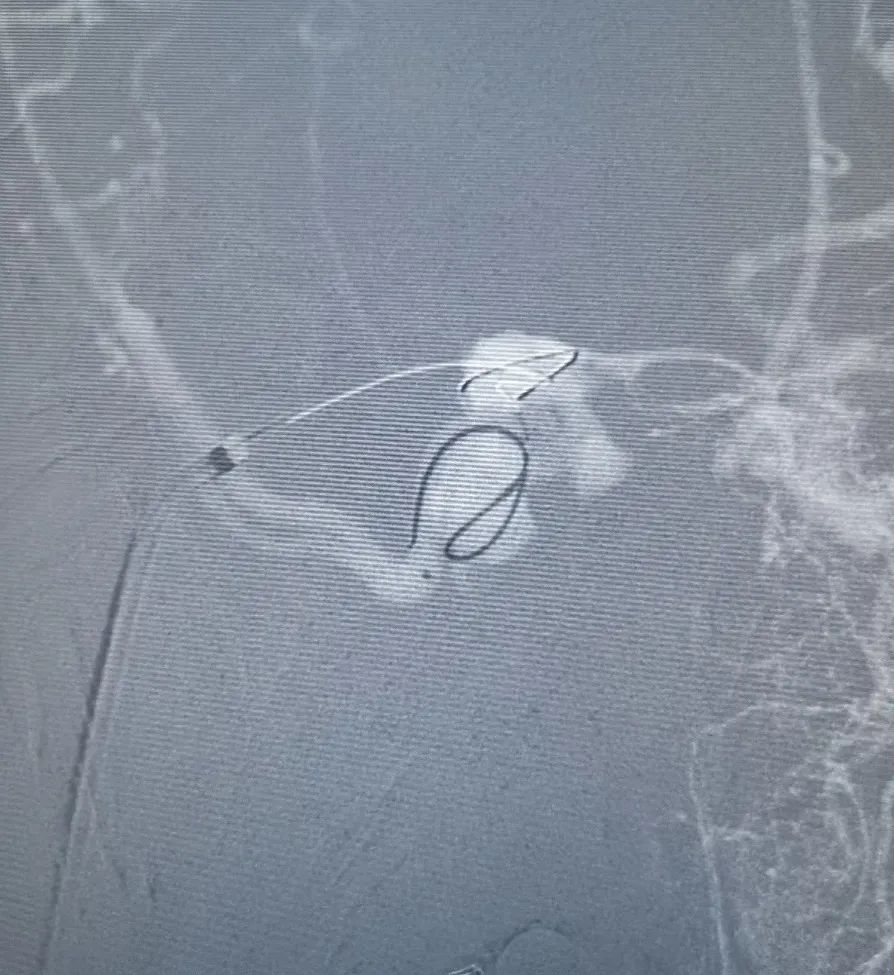

在Roadmap下,用0.014" 微导丝携第1根Echelon-10微导管超选通过开通的岩下窦进入海绵窦内,远端位于瘘口附近,微量造影证实微导管位置。

然后撤出泥鳅导丝,在Roadmap下,用0.014" 微导丝携第2根Echelon-10微导管超选通过开通的岩下窦进入海绵窦内,在3D造影辅助下选取工作角度,将第2根Echelon-10微导管成功超选至右侧蝶顶窦开口处,微量造影证实微导管位置。

调整第2根Echelon-10微导管位置后,先向蝶顶窦开口处填入Jasper®弹簧圈。

然后通过第1根微导管向瘘口处海绵窦注射Onyx栓塞剂。注射过程中通过造影导管在左侧颈外动脉反复造影,直至该海绵窦硬脑膜动静脉瘘完全不显影。最后做双侧颈总动脉造影,见右侧海绵窦硬脑膜动静脉瘘完全不显影,双侧颈内动脉、大脑中动脉、大脑前动脉及其它分支显影良好。行CT示颅内未见明显出血。

该患者眼上静脉无明显逆流,岩下窦不显影,可供选择的入路非常有限,需要开通岩下窦,所幸术中开通并不困难。术中蝶顶窦超选存在一定的困难,3D旋转可较清晰显示,必要时辅以3D路图。如介入开通岩下窦失败,可选的方案包括复合手术下开颅穿刺侧裂静脉等。

合理的治疗策略选择是手术成功的先决条件。对于该例海绵窦DAVF,我们首先选择闭塞蝶顶窦开口,以解决侧裂静脉逆流的问题,降低后期的出血风险,然后才着手栓塞瘘口。这需要置入两根微导管,增加了手术难度。如果能用单微导管完美地精准栓塞瘘口而无需先栓塞静脉开口,不失为更好的选择,但需警惕栓塞材料弥散至侧裂静脉,引起闭塞。

良好的通路建立为手术的顺利实施奠定了坚实的基础。本例采用加奇生物 Heralder® DA远端通路导管置于颈内静脉,可提供良好的支撑并利于术中岩下窦的开通及微导管超选海绵窦。该导管的性能较为优越,在其他的如动脉瘤病例中,我们常将该导管超选至海绵窦段以提供足够的支撑,从而使系统稳定,帮助使用Jasper®弹簧圈等栓塞材料按预定栓塞策略完成治疗,达到满意的栓塞效果。